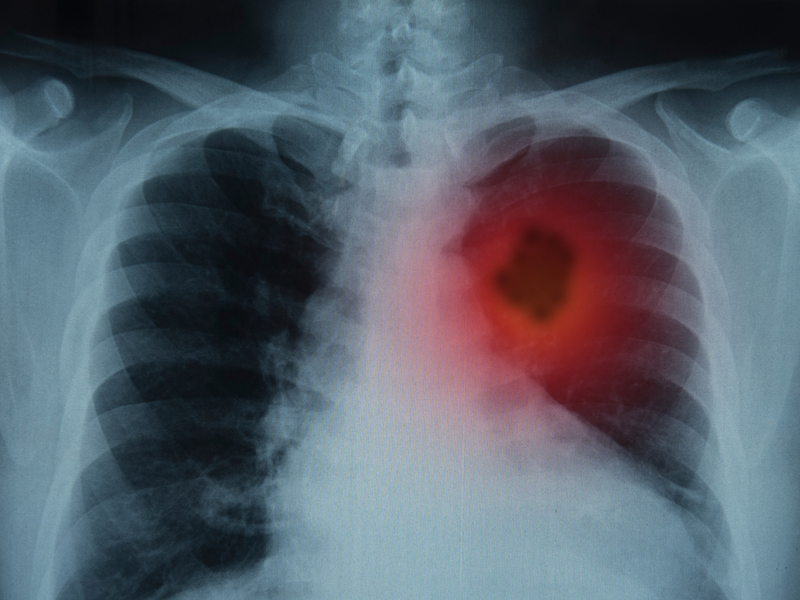

據世界衛生組織下屬的國際癌症研究機構發佈的全球癌症數據顯示, 2020 年全球新增癌症病例約 1930 萬,肺癌發病率佔到全球新增癌症病例的 11.4%,位居癌症發病數第二位。

眾所周知,吸煙與肺癌的發生息息相關。煙草燃燒後,可產生 4000 多種化學物質,其中至少 60 種有致癌的可能性。吸煙者發生肺癌的風險是不吸煙者的 20 倍,而二手煙同樣會增加 20%-30% 的患病風險。